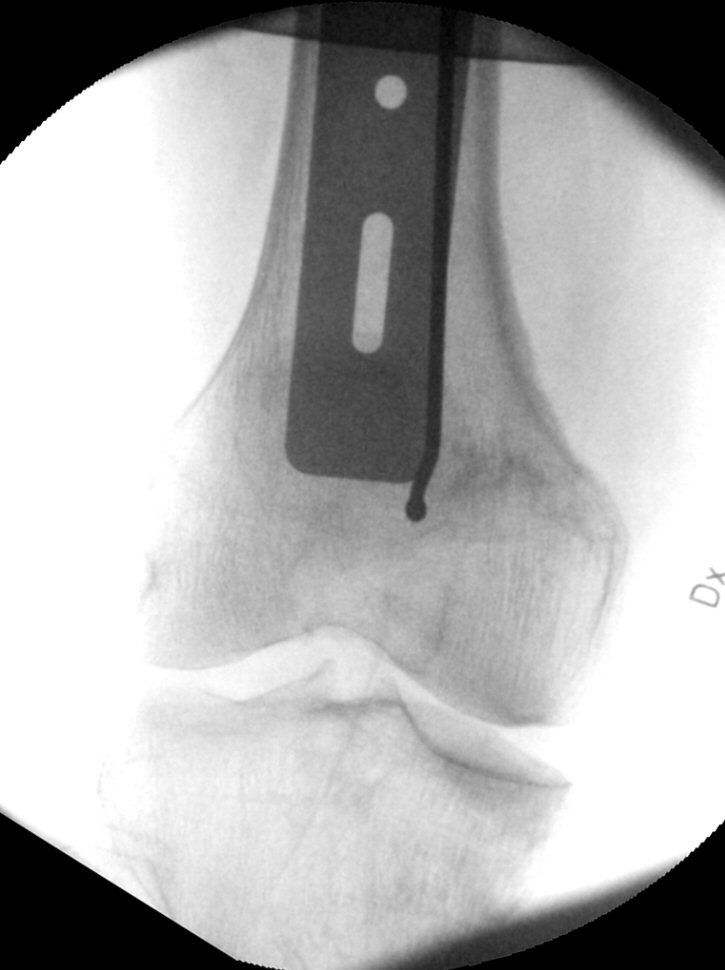

Frontalbild, mall i genomlysning

- Vrid mallen ca 90°. Titta i sidovy. Vrid spiken och justera mallen så den passerar märgspikens hål för glidskruv och hamnar motsvarande centralt i kollum och kaput.

Sidobild, mall i genomlysning, märgspikens glidskruvshål markerat med röd cirkel